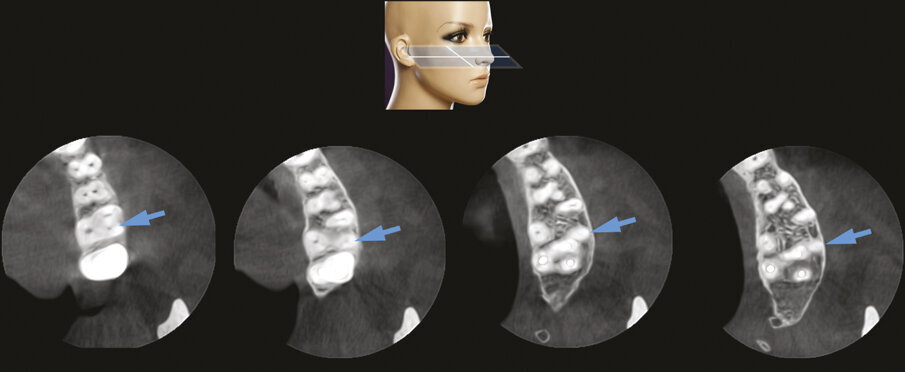

Fig. 2e - Le quattro sezioni assiali mostrano come la radice distovestibolare del primo molare sia vestibolare rispetto alla radice mesiovestibolare del secondo molare. Questa particolare situazione anatomica rappresenta una ovvia controindicazione all’approccio chirurgico.